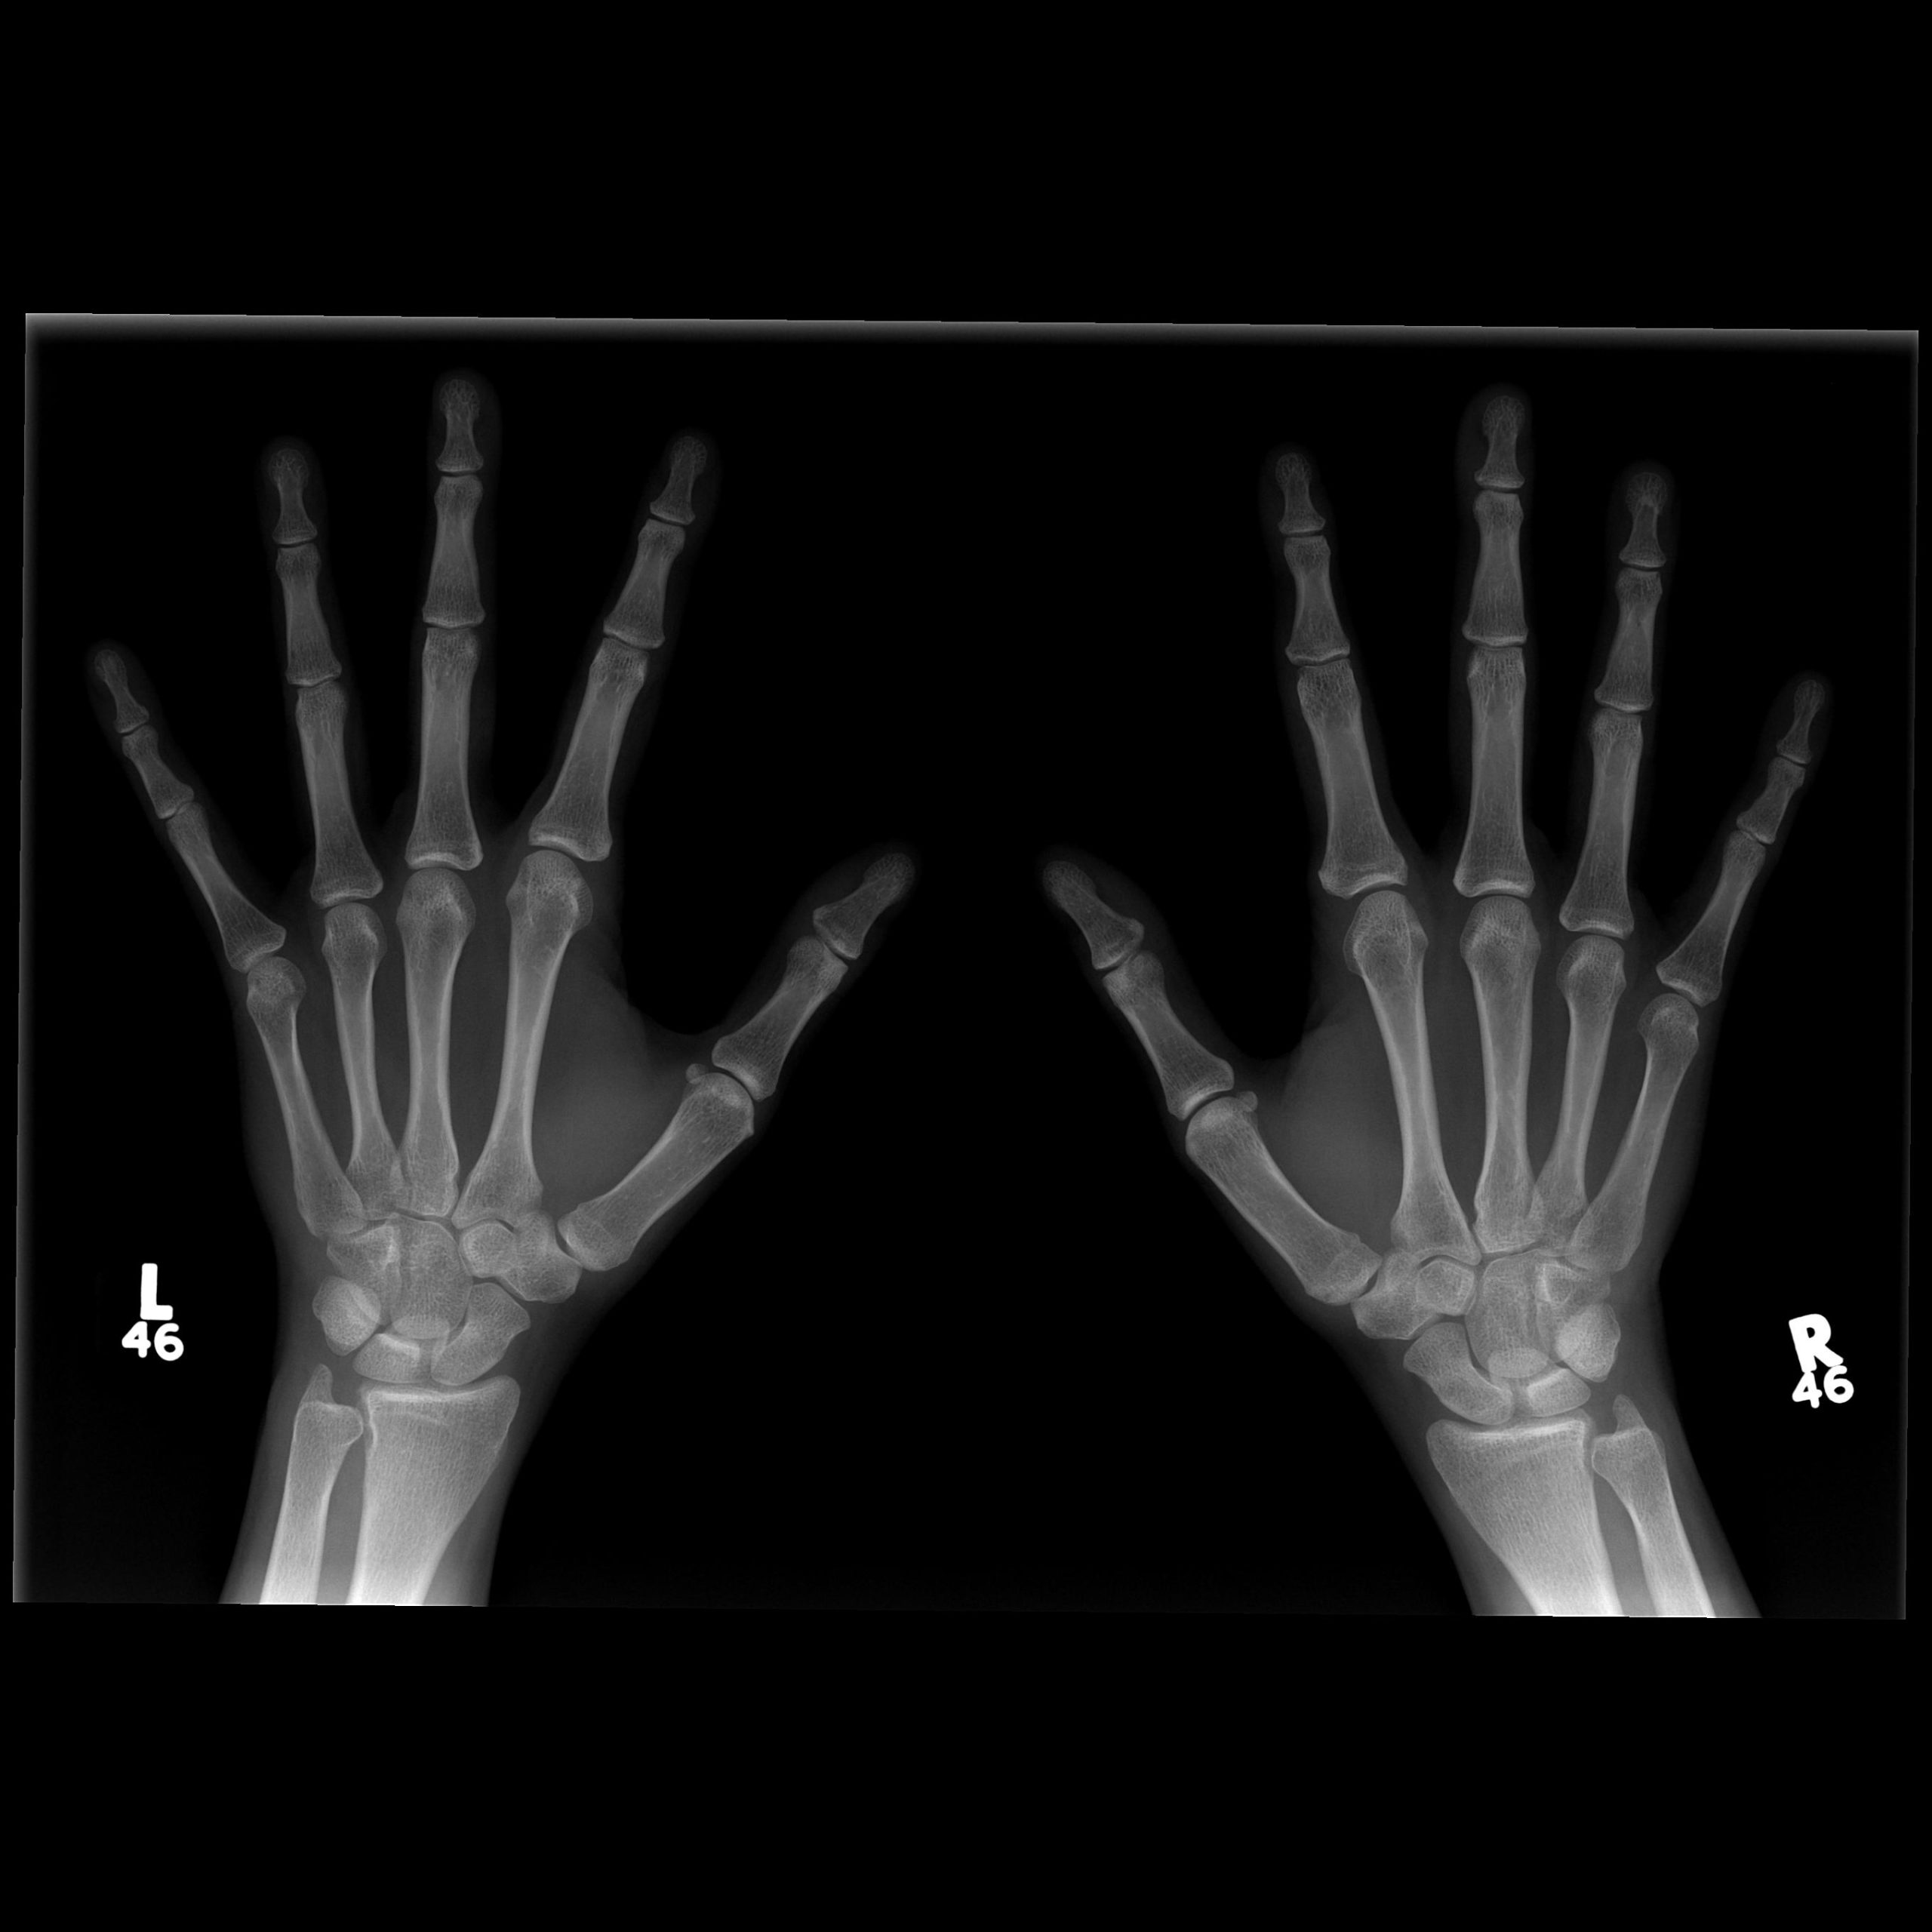

Normal Hand X Ray

A Hand X Ray is a non-invasive diagnostic procedure that uses a small, controlled amount of ionizing radiation to create images of the bones within the hand. The human hand is a complex structure consisting of 27 distinct bones, including the carpals of the wrist, the metacarpals of the palm, and the phalanges of the fingers. Because of this complexity, obtaining a clear image is essential for pinpointing the exact location of injury or disease.

During the procedure, the hand is positioned on an imaging plate. A beam of radiation is directed at the area, and because bone is denser than the surrounding soft tissue, it absorbs more of the radiation. This causes the bones to appear white on the image, while soft tissues appear in shades of gray, and empty space or gas appears black. This contrast allows medical professionals to assess structural integrity with high precision.

• Bone Alignment: Checking if the bones are in their anatomical position or if a displacement has occurred.

• Cortical Integrity: Searching for breaks or "step-offs" in the outer layer of the bone.

• Joint Space: Evaluating the distance between bones to determine if cartilage has worn away.

• Soft Tissue Swelling: Sometimes, even if the bone is intact, the image will show swelling in the surrounding tissue that indicates a soft tissue injury.